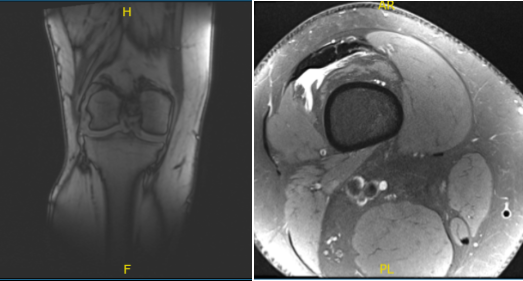

An MRI and X-ray were performed, which shows lateral meniscus tear. We discussed treatment options and the patient opted for surgical management. We discussed the risks and benefits and complications of the surgery. We discussed possible meniscal repair versus meniscectomy. The patient understood and signed an informed consent.

Arthroscopic surgery was performed. Lateral anterior portal was made for arthroscopic viewing. The scope was entered and the camera was entered. The camera showed a tear of the posterior horn and brought the posterior body of the lateral meniscus around the popliteal hiatus at its periphery.

The tear was repairable and I decided to repair it. There was a grade 2 to grade 3 chondral lesion over the patella as well as lateral condyle of the femur. Chondroplasty was performed. The meniscal rasp was used to prepare the capsular as well as the meniscal attachment.